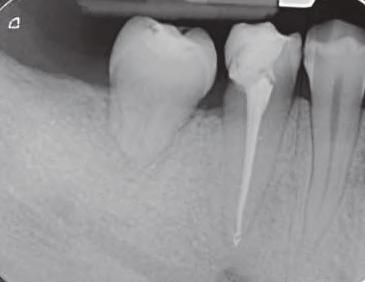

Figura: 3. Implanturile înclinate pot să se adapteze la osul non-alveolar în regiunea interantrală și pterigo-maxilară pentru a evita o procedură de grefare a sinusului.

osoasă pentru max larele atrof ate. Un mplant d stal încl nat poate perm te ut l zarea unu a ma lung ș obț nerea une poz ț onăr ma poster oare a acestu a. Teor a d n spatele acestu concept cons deră că d stanțele ma mar între mplantur le anter oare ș posteroare ar d str bu ma b ne forțele ocluzale; astfel, forța transversală exerc tată asupra mplantur lor încl nate nu ar f noc vă pentru acestea. La max lar, mplanturle d stale ar putea benef c a, de asemenea, de pereț osoș cort cal a s nusur lor ș foselor nazale. Pr n urmare, mplantur le pot f plasate cu or entăr încl nate, în loc de ax ale, pentru a angaja osul cort cal rez dual în toate d recț le, cum ar f în palat, pereț anter or ș poster or a s nusulu max lar ș tuberoz tatea max lară. Implantur le încl nate, cu d verse des gnur macro se pot adapta, de asemenea, la osul anatom c nonalveolar în reg un le paranazale/ nterantrale ș pter gomax lare, precum ș la osul z gomat c (f g. 3).